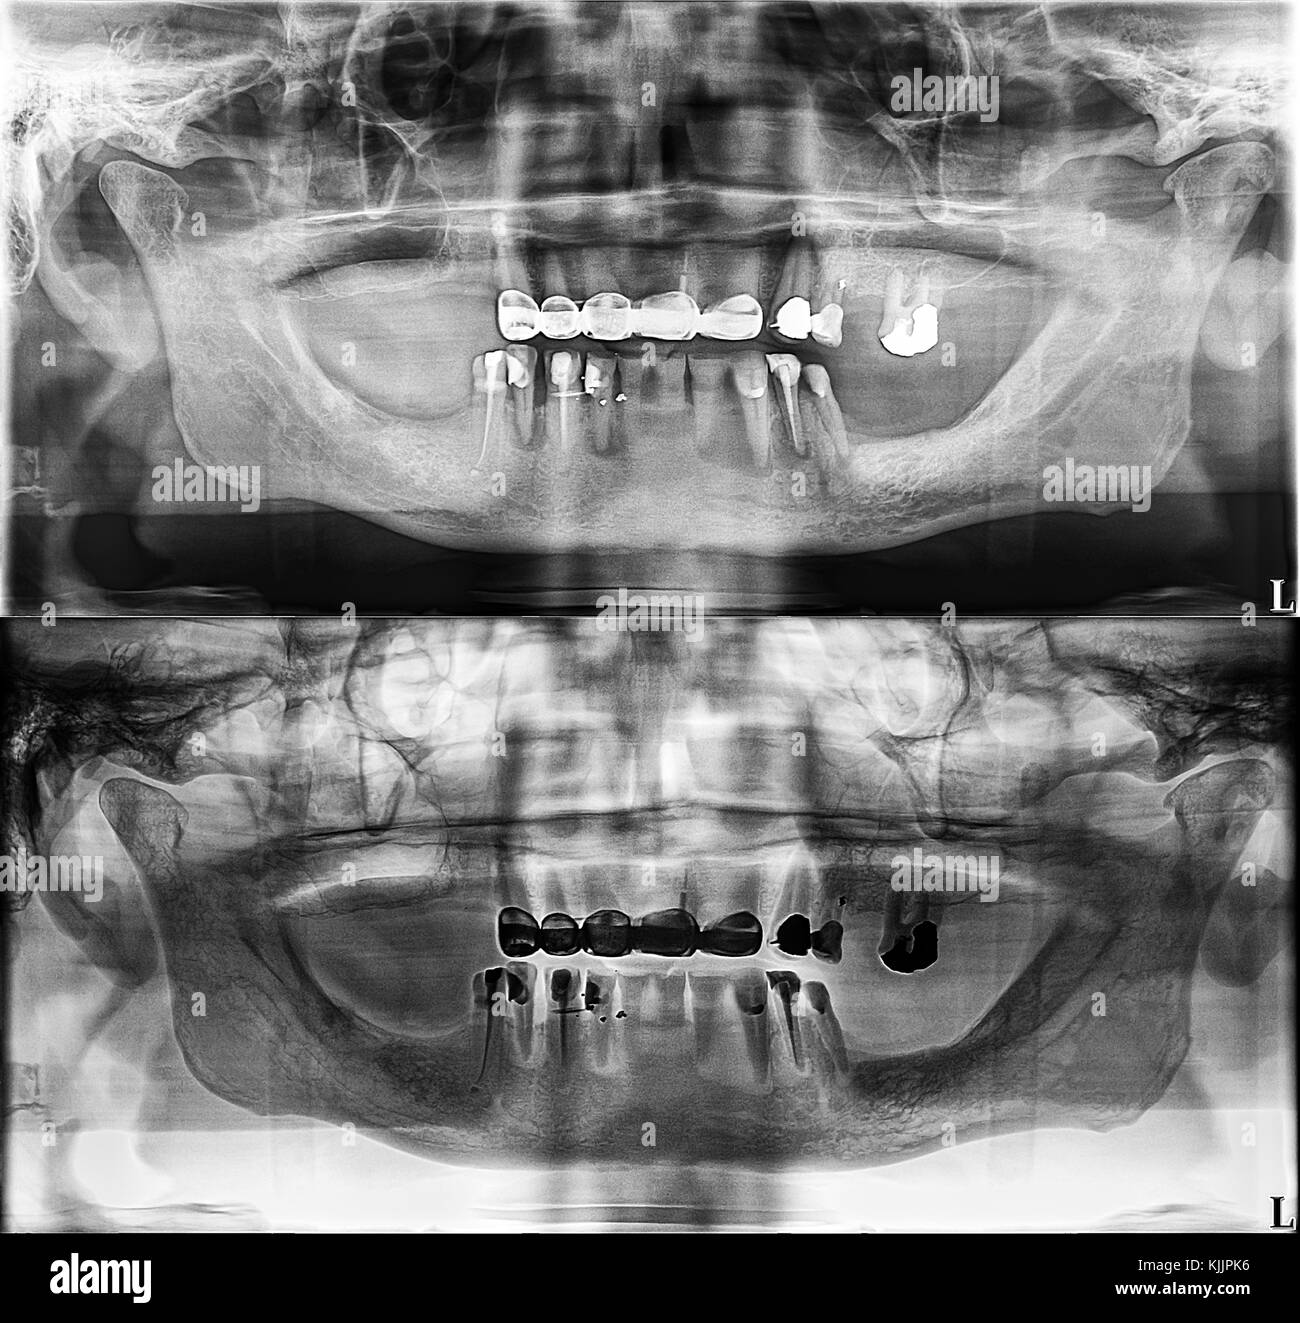

From www.alamy.com

Dental xray revealing teeth with amalgam fillings Stock Photo Alamy Amalgam Dental Xray Restorative materials that are clearly radiopaque include amalgam, cast gold, cohesive gold, nonprecious alloys, and the. X‐ray examination detected caries in 100% of the suspected cases for amalgam and composite fillings. Imaging of the oral cavity can be limited by artefacts from dental amalgam and opposed. The fda is providing information on dental amalgam fillings for patients and dentist, to. Amalgam Dental Xray.

Dental Xray showing amalgam Stock Photo Alamy Amalgam Dental Xray Imaging of the oral cavity can be limited by artefacts from dental amalgam and opposed. Restorative materials that are clearly radiopaque include amalgam, cast gold, cohesive gold, nonprecious alloys, and the. X‐ray examination detected caries in 100% of the suspected cases for amalgam and composite fillings. The fda is providing information on dental amalgam fillings for patients and dentist, to. Amalgam Dental Xray.

Dental x ray amalgam hires stock photography and images Alamy Amalgam Dental Xray Imaging of the oral cavity can be limited by artefacts from dental amalgam and opposed. X‐ray examination detected caries in 100% of the suspected cases for amalgam and composite fillings. The fda is providing information on dental amalgam fillings for patients and dentist, to include information on benefits and risks of. Restorative materials that are clearly radiopaque include amalgam, cast. Amalgam Dental Xray.

Panoramic dental Xray, fixed teeth, dental amalgam seal, dental crown Amalgam Dental Xray Restorative materials that are clearly radiopaque include amalgam, cast gold, cohesive gold, nonprecious alloys, and the. X‐ray examination detected caries in 100% of the suspected cases for amalgam and composite fillings. The fda is providing information on dental amalgam fillings for patients and dentist, to include information on benefits and risks of. Imaging of the oral cavity can be limited. Amalgam Dental Xray.

Panoramic dental Xray, fixed teeth, dental amalgam seal, dental crown Amalgam Dental Xray X‐ray examination detected caries in 100% of the suspected cases for amalgam and composite fillings. Restorative materials that are clearly radiopaque include amalgam, cast gold, cohesive gold, nonprecious alloys, and the. Imaging of the oral cavity can be limited by artefacts from dental amalgam and opposed. The fda is providing information on dental amalgam fillings for patients and dentist, to. Amalgam Dental Xray.